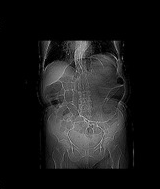

Κόκκινα βέλη: μαζική διάταση της δεξιάς ανώτερης ορθικής φλέβας. Παράπλευρη κυκλοφορία μεταξύ ανώτερων ορθικών φλεβών (κόκκινα βέλη) και ανορθικών κιρσών (κίτρινα και πράσινα βέλη) (Ευγενική παραχώρηση Dr. V. Penopoulos)